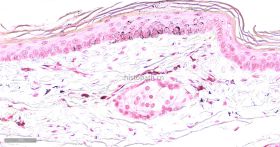

Masson-Fontana黑色素染色染色原理:

黑色素属于非血源性内生色素,是一组由黑色素母细胞产生的颜色从浅棕色到黑色的色素,这种色素通常出现在皮肤表皮、眼睛、大脑的黑质和毛囊中。黑色素有一个显著的物理性质,即完全不溶解于大多数有机溶剂--几乎可以肯定是由于黑素体中已形成的黑色素可与蛋白质紧密结合;黑色素另一个物理性质是能够被强氧化剂漂白,尽管这个过程是缓慢的,在病理情况下,这种色素也可出现在良性痣细胞瘤中和恶性黑色素瘤中,在常规HE染色中不呈黑色而是呈棕黄色或棕黑色,许多方法可用于识别黑色素和黑色素生成细胞,如还原方法,如Masson-Fontana银技术和Schmorl三价铁-铁氰化钾还原实验;酶方法(如多巴反应);荧光方法:免疫组织化学。

Masson-Fontana黑色素染色液是利用黑色素具有将银氨溶液还原为金属银特性即嗜银反应原理来显示黑色素,染色后黑色素呈黑色,该法属于常用的黑色素特殊染色法,效果较其他染色理想。

染色结果: